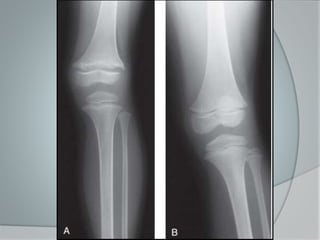

Radiología

 Deformidades , en forma de

incurvaciones o arqueamientos, en

especial en extremidades inferiores.

 Fracturas en tallo verde

Radiología  Deformidades, en forma de incurvaciones o arqueamientos, en especial en extremidades inferiores.  Fracturas en tallo verde